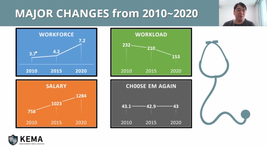

“응급의학 전공의 수련중도포기 높은 이유 개선 필요”

- 2021-11-05 06:00

- 신대현 기자